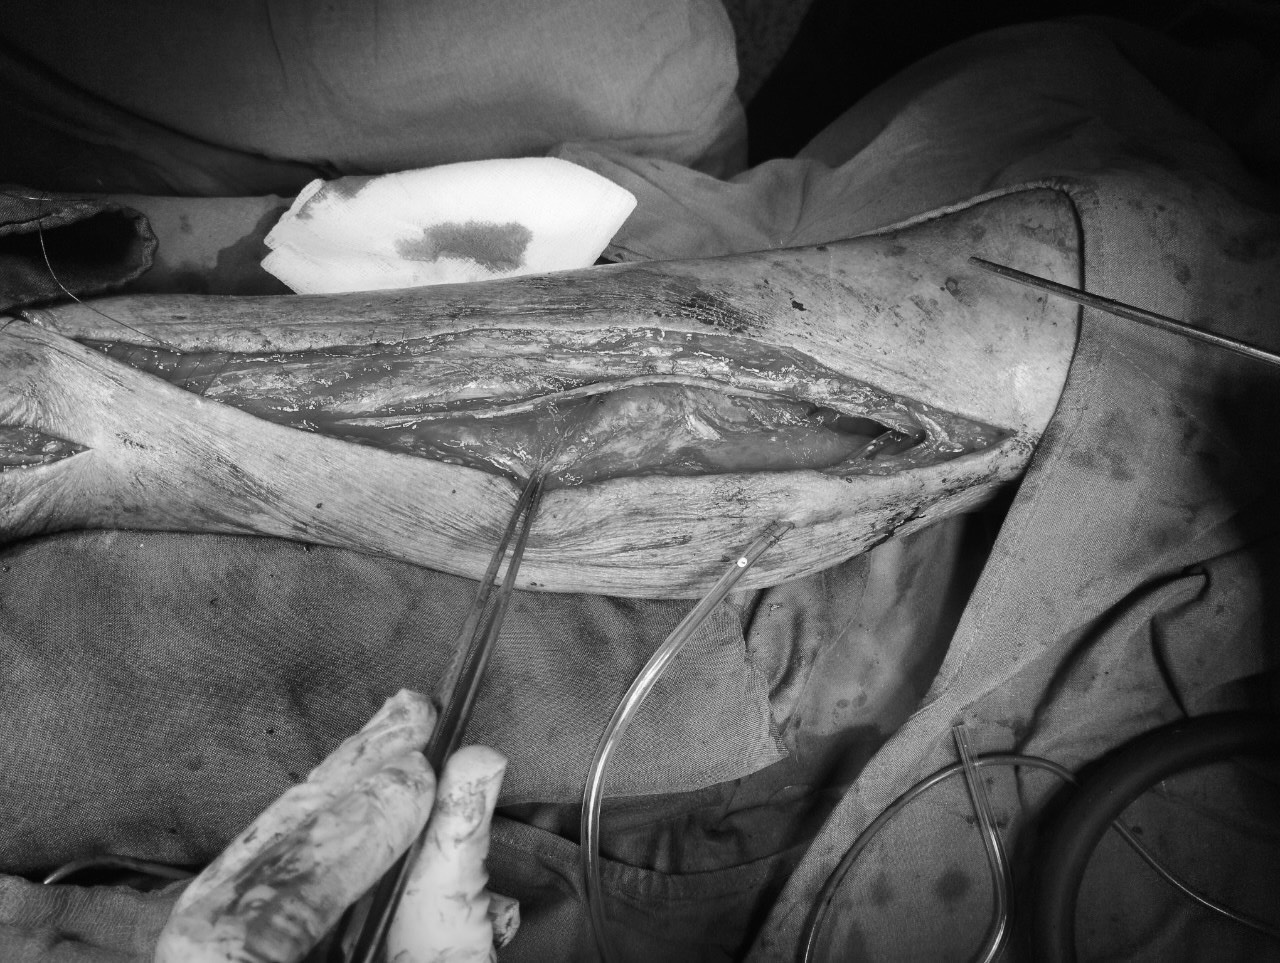

Hình ảnh trong lúc mổ. Ảnh BS cung cấp

Ca phẫu thuật do Tiến sĩ, bác sĩ. Nguyễn Lương Tấn-Phụ trách khoa Ngoại lồng ngực của Bệnh viện cùng ê kíp thực hiện. Ca mổ diễn ra theo kế hoạch, tĩnh mạch hiển lớn tự thân trở thành thân động mạch mới, bàn chân phải hồng ấm trở lại. Một tuần sau mổ chân phải bệnh nhân phục hồi tốt, hết đau nhức, bệnh nhân đã có thể đi lại nhẹ nhàng, vết loét hoại tử đầu ngón chân bắt đầu có dấu hiệu liền sẹo. bệnh nhân tự mình bước đi trong bệnh viện khi trở lại tái khám lần đầu sau mổ với tinh thần lạc quan cho sức khỏe, vận động.